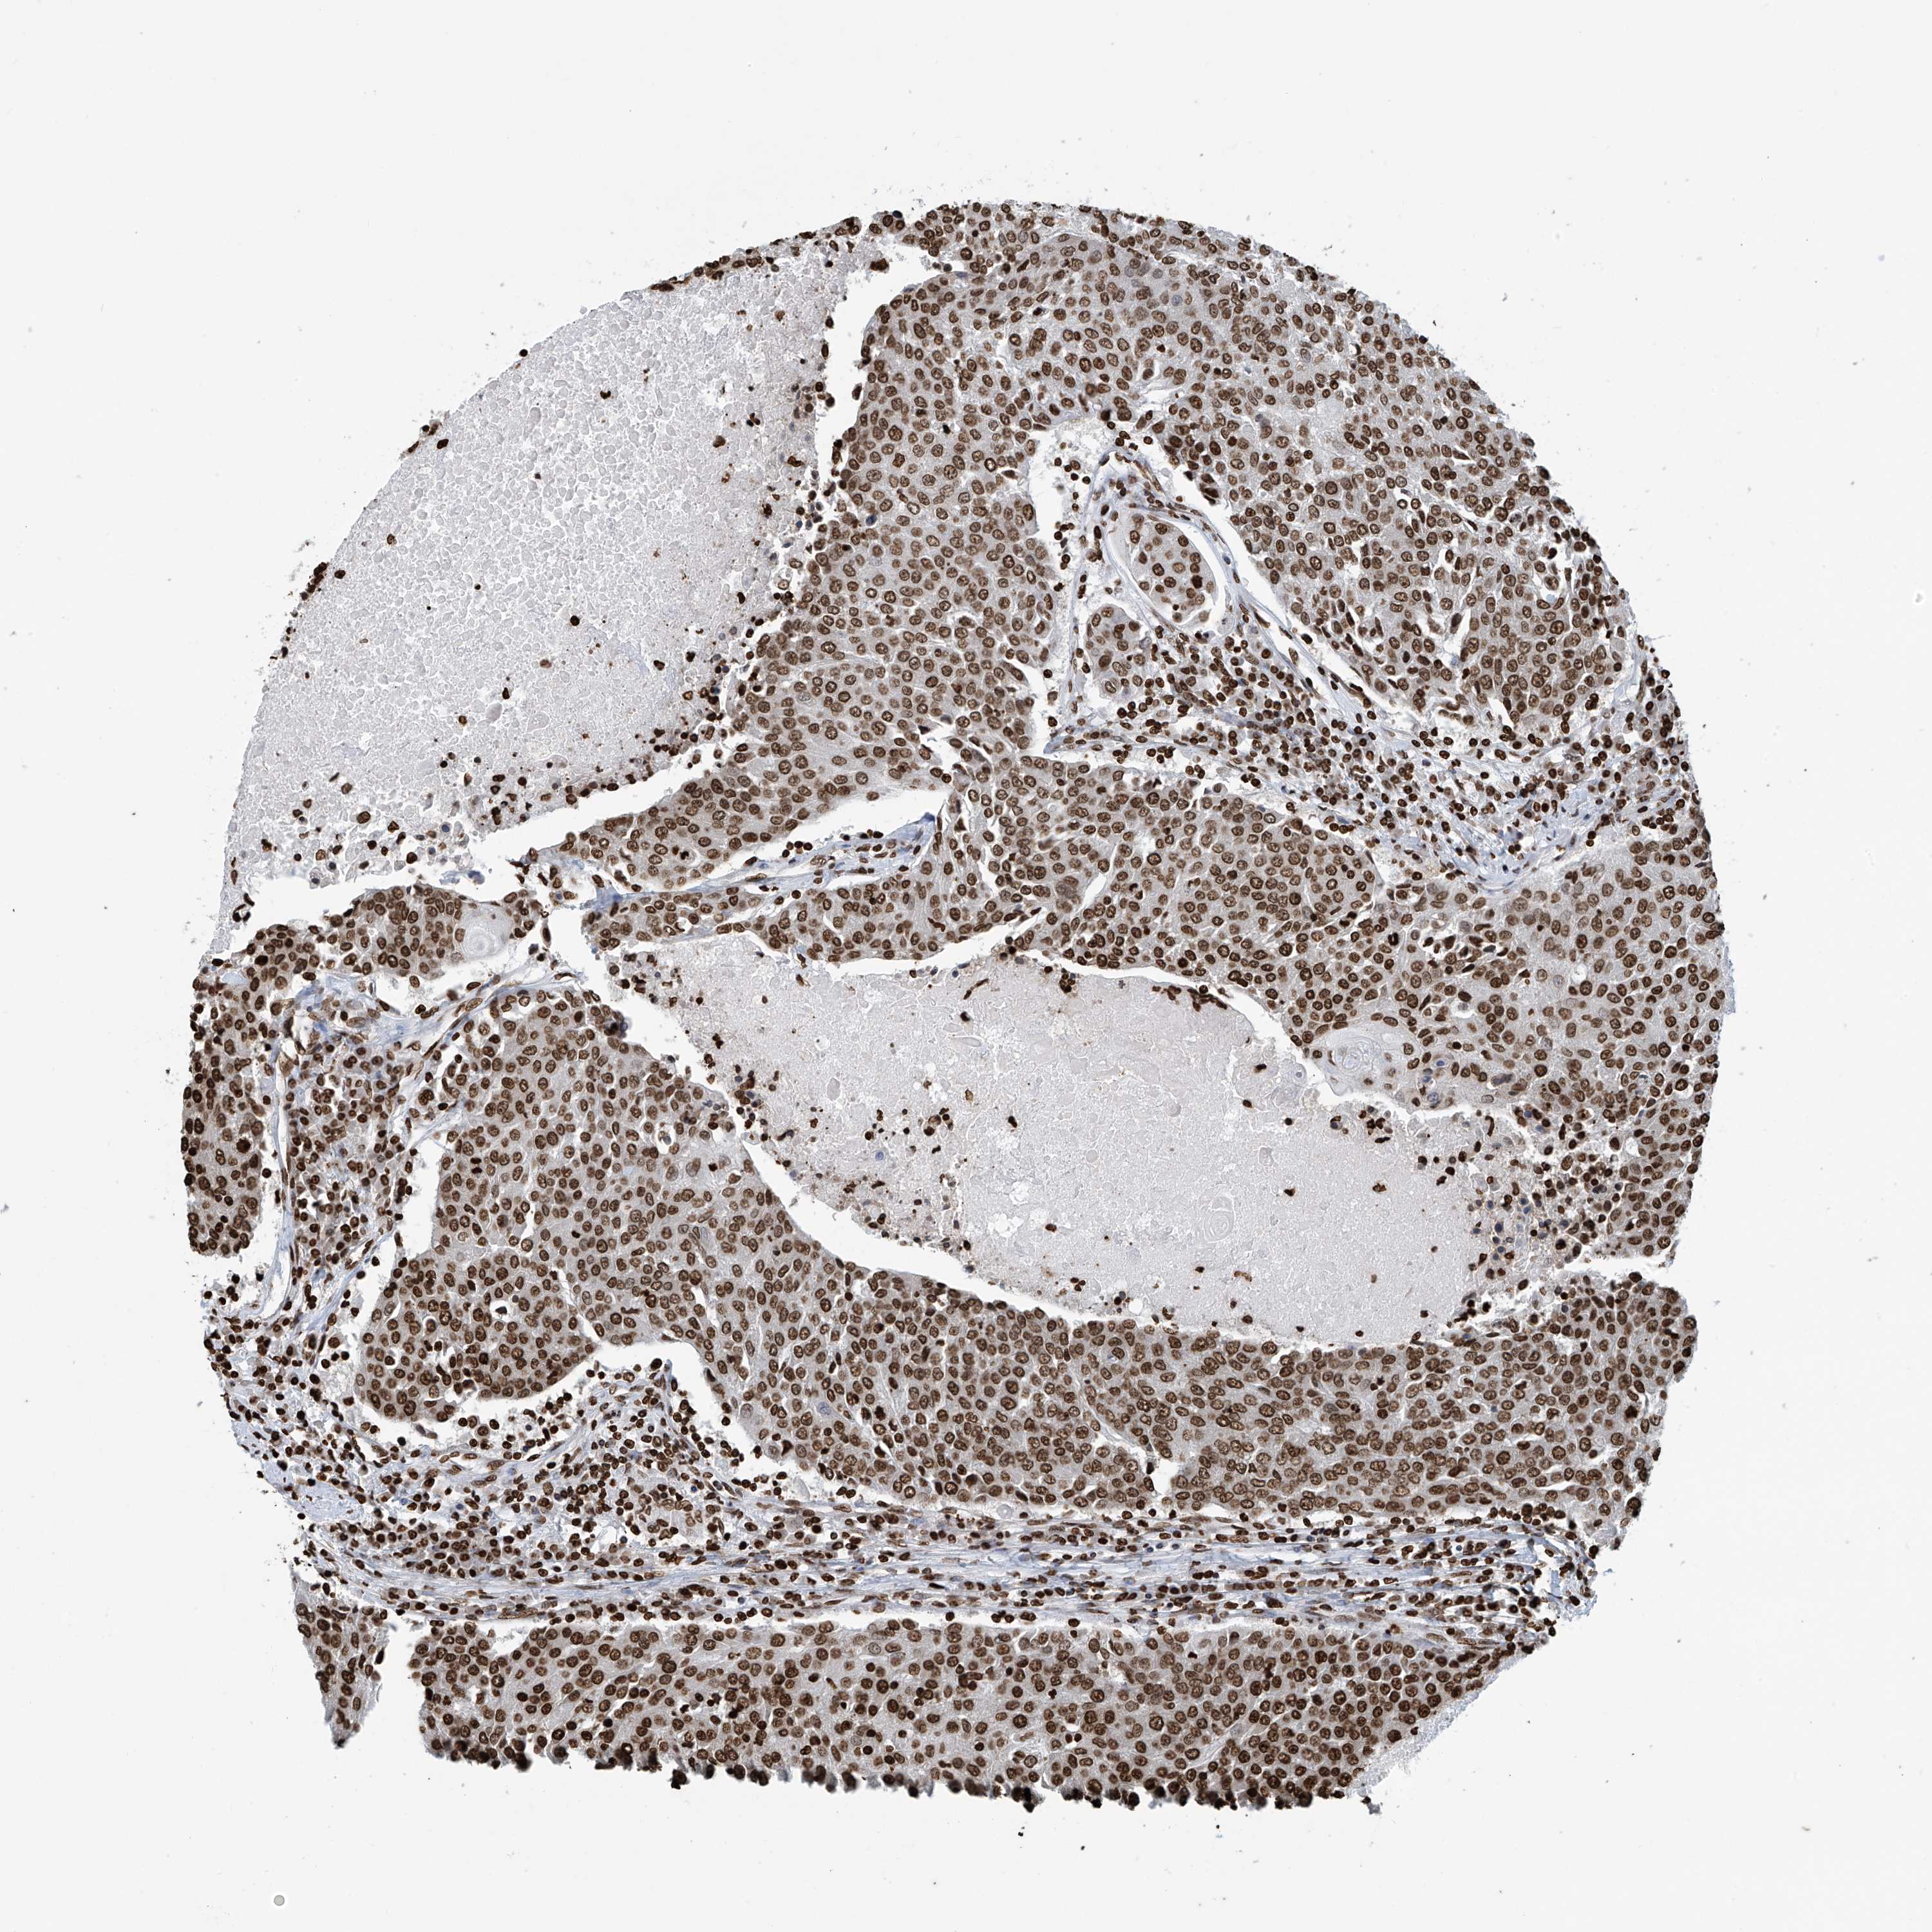

UROTHELIAL CANCER - Protein expressioni

A mouse-over function shows sample information and annotation data. Click on an image to view it in a full screen mode. Samples can be filtered based on level of antibody staining by selecting one or several of the following categories: high, medium, low and not detected. The assay and annotation is described here.

Note that samples used for immunohistochemistry by the Human Protein Atlas do not correspond to samples in the TCGA dataset.

Antibody stainingi

Antibody staining in the annotated cell types in the current human tissue is reported as not detected, low, medium, or high, based on conventional immunohistochemistry profiling in selected tissues. This score is based on the combination of the staining intensity and fraction of stained cells.

Each image is clickable and will lead to virtual microscopy that enables deeper exploration of all samples and also displays staining intensity scores, fraction scores and subcellular localization as well as patient and tissue information for each sample.

Antibody HPA036134

Staining

High

Medium

Low

Not detected

Intensity

Strong

Moderate

Weak

Negative

Quantity

>75%

75%-25%

<25%

None

Location

Nuclear

Cytoplasmic/membranous

Cytoplasmic/membranous,nuclear

Urothelial carcinoma, Low grade

Urothelial carcinoma, High grade